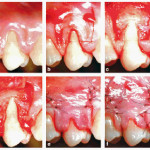

Recessioni gengivali

Questo aggiornamento passa in rassegna le diverse possibilità di intervento in caso di recessioni gengivali.

Lembo con riposizionamento coronale: una proposta chirurgica modificata per la...